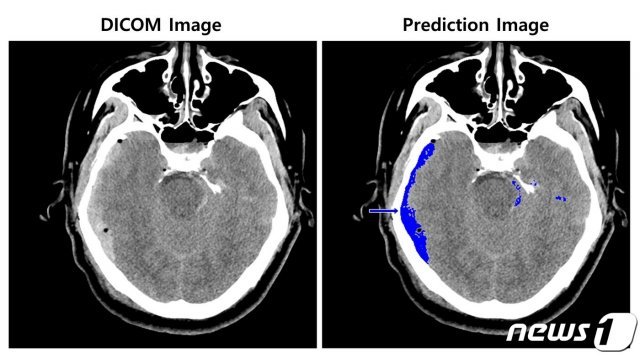

(SK㈜ C&C 제공)© 뉴스1

SK㈜ C&C는 1차 아주대학교의료원에 이어 2차로 서울대학교병원의 CT 영상을 활용해 ‘뇌출혈 영상 판독 AI모델’을 개발했다. 이 모델 학습에는 SK㈜ C&C 비전 AI의 이미지 세그멘테이션 기술과 총 8만여장의 뇌 CT 영상 및 판독데이터를 활용했다.

이미지 세그멘테이션 기술은 비전 AI 기술 중 해당 객체가 어떤 형상으로 존재하는지를 픽셀 단위로 인식해 객체의 위치를 구분해 내는 기술이다.